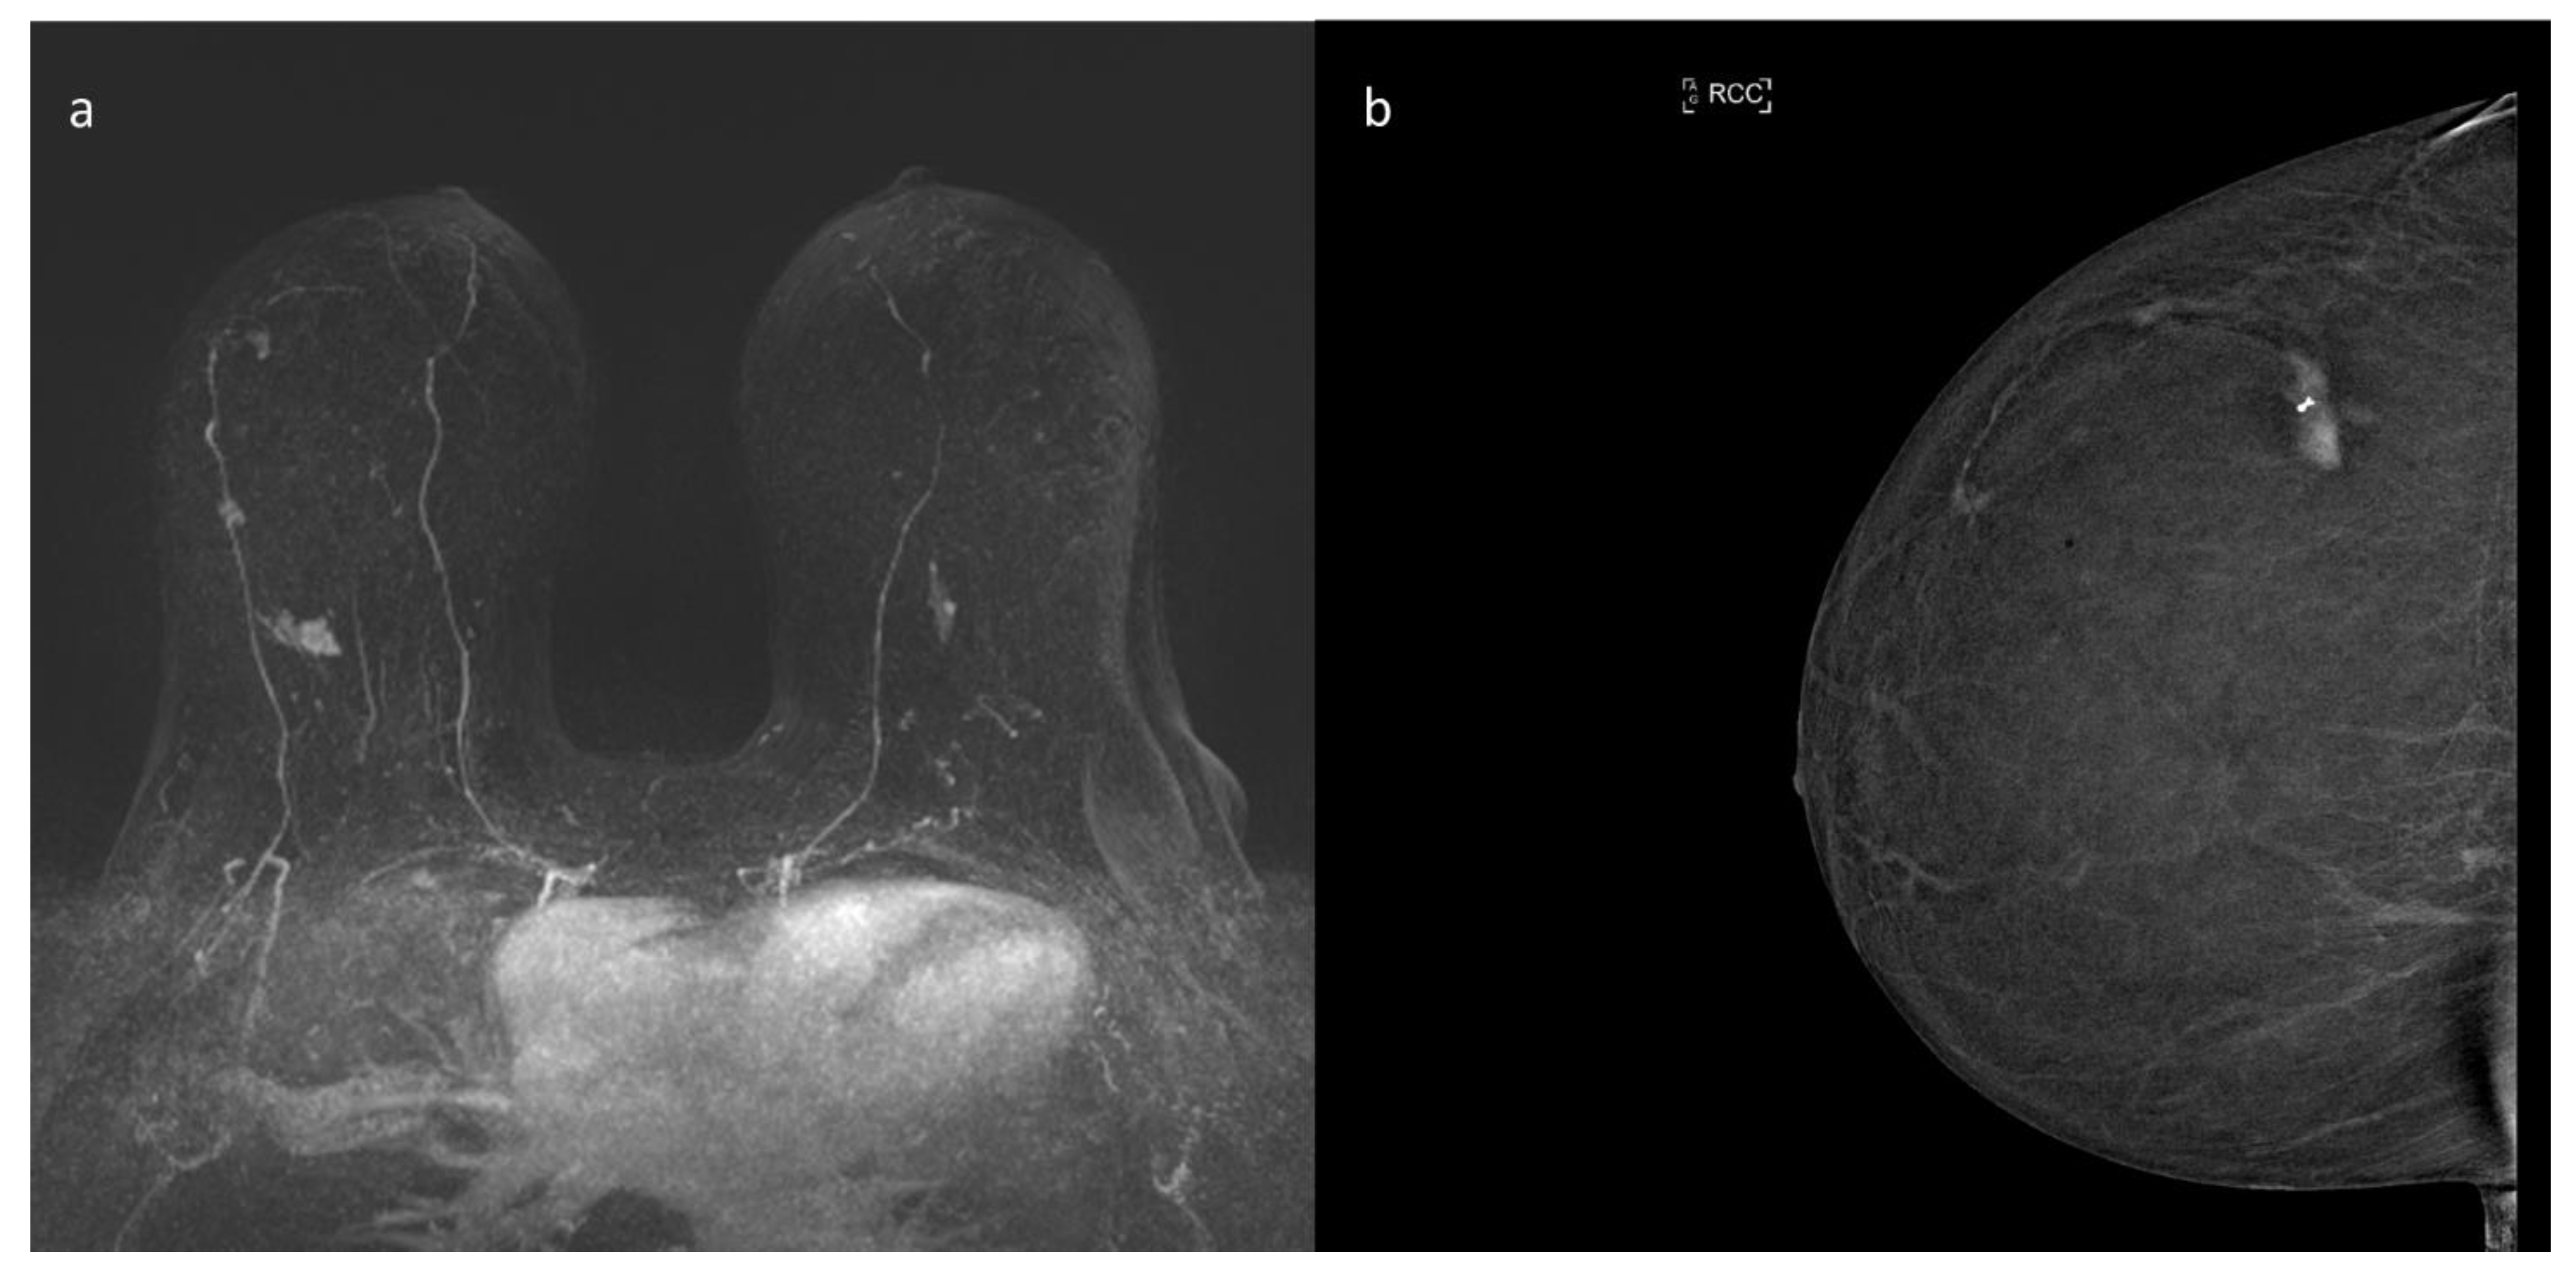

9. ce-MRI

10. Contrast Enhanced Mammography (CEM)

- Mann, R.M.; Cho, N.; Moy, L. Breast MRI: State of the Art. Radiology 2019, 292, 520–536. [Google Scholar] [CrossRef] [PubMed]

- Jochelson, M.S.; Dershaw, D.D.; Sung, J.S.; Heerdt, A.S.; Thornton, C.; Moskowitz, C.S.; Ferrara, J.; Morris, E.A. Bilateral contrast-enhanced dual-energy digital mammography: Feasibility and comparison with conventional digital mammography and MR imaging in women with known breast carcinoma. Radiology 2013, 266, 743–751. [Google Scholar] [CrossRef]

- Łuczyńska, E.; Heinze-Paluchowska, S.; Hendrick, E.; Dyczek, S.; Ryś, J.; Herman, K.; Blecharz, P.; Jakubowicz, J. Comparison between breast MRI and contrast-enhanced spectral mammography. Med. Sci. Monit. 2015, 21, 1358–1367. [Google Scholar] [CrossRef] [PubMed]

- Fallenberg, E.M.; Schmitzberger, F.F.; Amer, H.; Ingold-Heppner, B.; Balleyguier, C.; Diekmann, F.; Engelken, F.; Mann, R.M.; Renz, D.M.; Bick, U.; et al. Contrast-enhanced spectral mammography vs. mammography and MRI-clinical performance in a multi-reader evaluation. Eur. Radiol. 2017, 27, 2752–2764. [Google Scholar] [CrossRef]